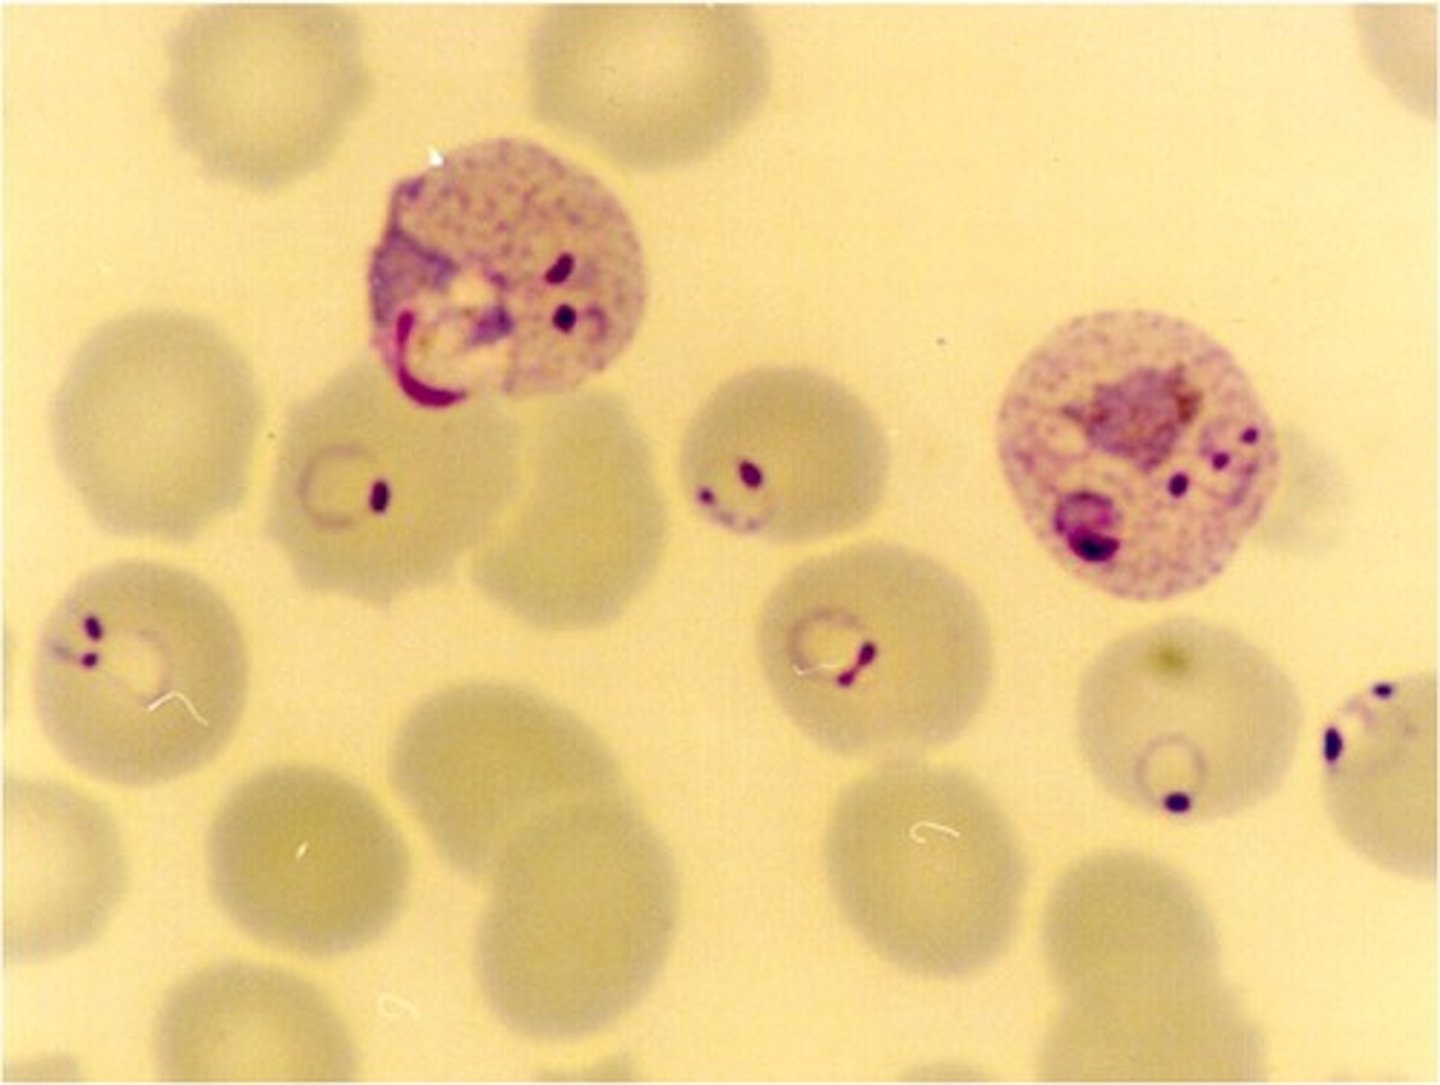

trypanosomes

exotic

haemoproteus

exotic hemoparasite

nucleus is "embraced" not "displaced"

via blood sucking insects

plasmodium

exotic hemoparasite

causes avian malaria

via mosquitoes